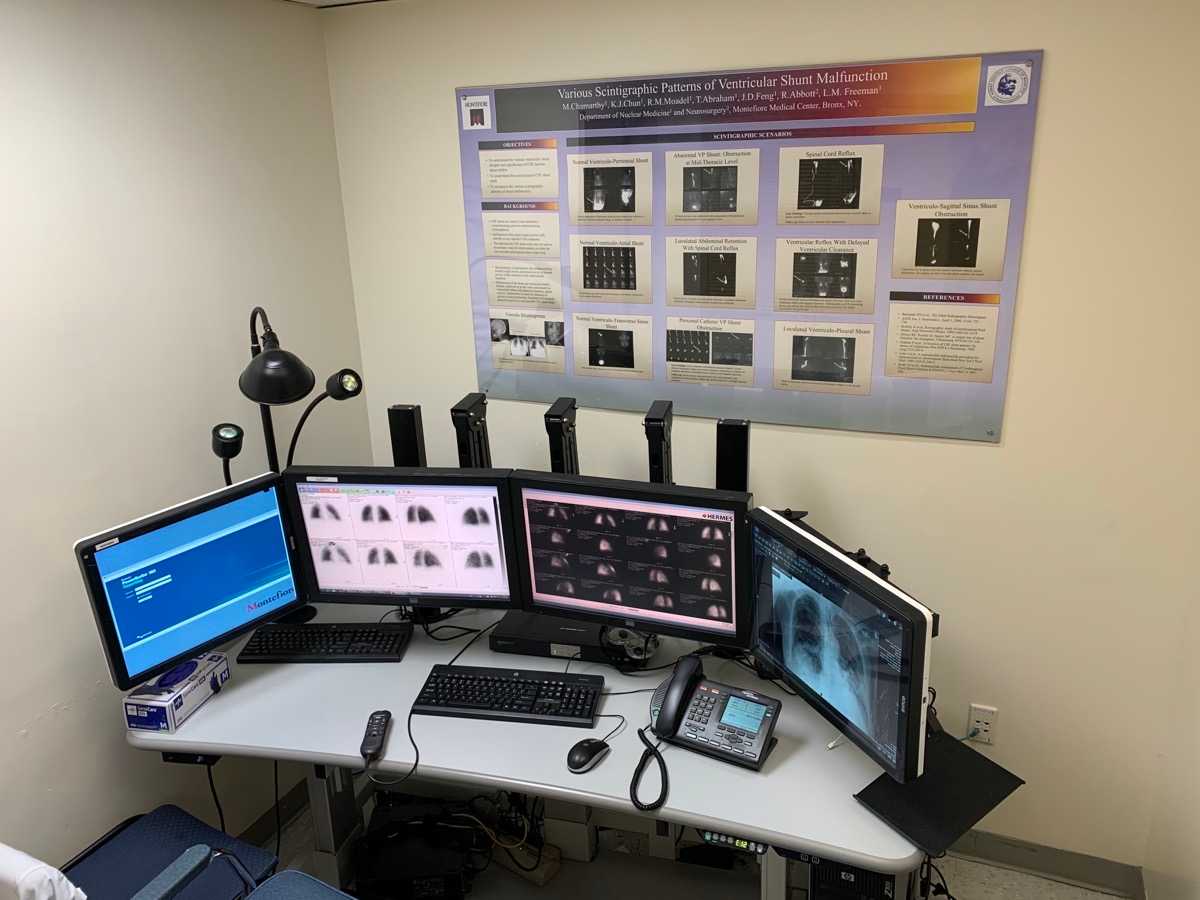

Moses Campus, along with Children’s Hospital at Montefiore Einstein, features 726 adult inpatient beds and 106 pediatric inpatient beds. The facility also offers services to outpatients. As an NCI-Designated Cancer Center, Moses provides diagnostic and therapeutic modalities through an active theranostics program. While training at Moses, residents partake in a particularly rigorous program in oncologic and non-oncologic pediatric and adult nuclear medicine. Our Transplant Center, also on-site, affords residents the ability to evaluate organ physiology pre- and post-transplant.

Our 431-bed Jack D. Weiler Hospital is located adjacent to the Albert Einstein College of Medicine in the Morris Park section of the Bronx. While at Weiler, residents participate in independent, hands-on training, with a particular focus on emergency cases and nuclear cardiology studies overseen by an attending. Residents are also exposed to much of their on-call experience at this location.